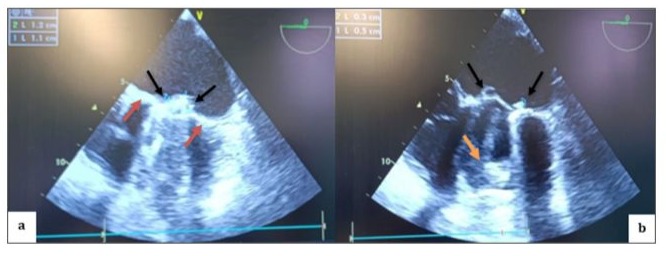

General anesthesia induced: 250 µg fentanyl, 0.3 mg/kg etomidate, and 1.2 mg/kg rocuronium. Anesthesia maintained with sevoflurane (MAC = 1.0). Analgesia maintained: 250 µg fentanyl boluses every 30–40 min; blood gas analysis 10 min after intubation. TEE probe inserted using video laryngoscope. Patient stable with low-dose vasoactive support before cardiopulmonary bypass. Doppler ultrasound in Scarpa triangle to study femoral vein and artery, found to be patent but small in size, especially femoral artery (8 mm). TEE performed pre-sternotomy to define anesthesia and surgical strategy, evaluate lesions, and address hemodynamic instability before CPB. Bicaval view used to monitor venous cannula progression. (video 1) Upon opening Scarpa triangle, common femoral artery was smaller than available venous cannulae. Central cannulation was decided upon, with TEE monitoring throughout. LV appeared small with limited opening of one valve leaflet and complete blockage of the other. Mitral valve apparatus identified with thrombi. Anterior and inferior walls of LV retained kinetics. Oblique plane revealed LV inflow chamber and outflow tract. Right ventricle was dilated with normal aortic ring. Leaking annuloplasty seen in right atrium. Left atrium, tricuspid valve, and right ventricle were thrombus-free. In mid-esophageal view, St. Jude mechanical valve had thickened ring with thrombi on both sides. (Figure 3) Pulsed Doppler TEE at the mechanical mitral valve in the mid-esophageal view, at a perpendicular plane of 60 degrees, showing a holosystolic retrograde mitral flow velocity of 1.3 m/s. (video 2) Slight probe rotation revealed left atrium dilation, thickened leaflets, limited leaflet movement at heart crux, and blockage at atrium-ventricle junction. Hyper-echoic thrombi in left ventricle were partly obscured. (Figure 3b) TEE in 2D mode, transducer at 45° counter clockwise rotation, shows dilated left atrium with obstructed mechanical valve due to multiple thrombi at leaflets, ring, and core. Leaflet opening beneath appendage is absent and limited on opposite side. Ring appears thickened with fibrinous thrombus. Reverberation echoes obscure left ventricle walls except for anterior and inferior walls with preserved kinetic activity (Video 3).

Figure 3: TEE in mid-esophageal view, transducer at 0 degrees, showing a thickened appearance of the St. Jude mechanical valve ring in an anatomical anti-position (a) (red arrow) with multiple thrombi on the atrial (a; b) (black arrow) and ventricular (b) (orange arrow) sides of both the internal and external leaflets.